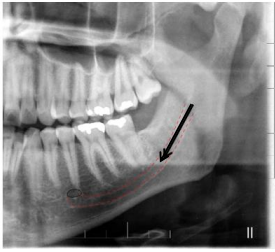

A radiografia panorâmica é a técnica extrabucal

mais solicitada em odontologia. Entre as suas

indicações estão a visão ampla do complexo

maxilomandibular, a avaliação da relação entre

dentes decíduos e permanentes, o

posicionamento de terceiros molares

inclusos/impactados, o estudo de anomalias

dentárias, a extensão de lesões patológicas e

alterações metabólicas, além do diagnóstico de

fraturas mandibulares e da ATM.

Fonte: Association between Facial Type and Mandibular Canal Morphology – Analysis in Digital Panoramic Radiograph..

Considerando a radiografia panorâmica apresentada, a estrutura anatômica indicada pela seta e pelo tracejado corresponde a: